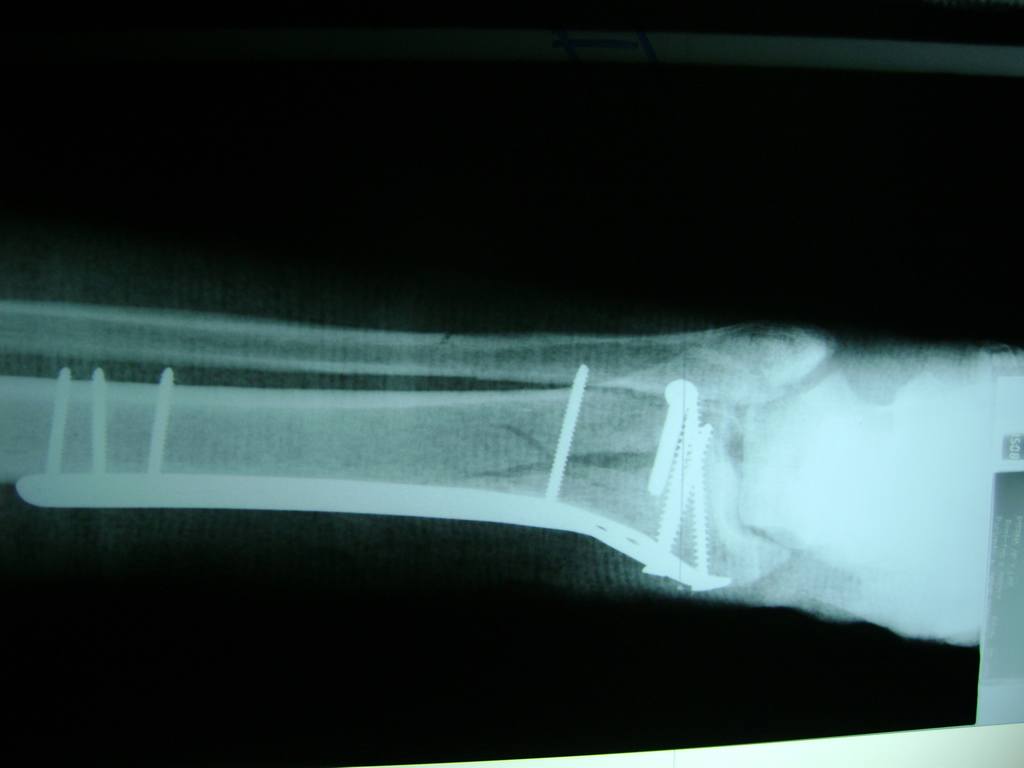

Aunque cada uno de estos huesos puede fracturarse por separado, normalmente la rotura es una lesión que se produce de forma conjunta

La mayor parte de las roturas implican a la parte proximal del hueso (parte del hueso próximo a la rodilla) o a la parte distal (parte del hueso cerca del tobillo).

Debido a la fina cobertura de piel que recubre la tibia y el peroné, las fracturas generalmente son abiertas, es decir, el hueso roto rasga la piel, atravesándola. Las fracturas de tibia y peroné generalmente se producen por un fuerte impacto o torsión.

De esta forma nos ponemos a tus órdenes, somos conocedores de estos tipos de problemas, visitarnos será un gusto el poderte ayudar. cualquier inquietud puedes escribirnos al correo Esta dirección de correo electrónico está siendo protegida contra los robots de spam. Necesita tener JavaScript habilitado para poder verlo.